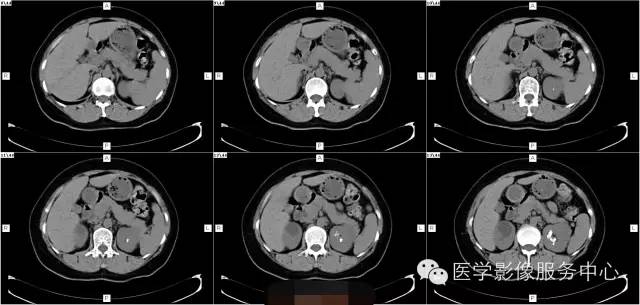

病史:

女,37岁,血尿一周

髓质海绵肾(简称MSK)又称Cacchi Ricci disease,是一种先天发育性肾髓质囊性病变,发生率约1:2000-5000,多见于40-60岁男年,70%为双侧肾脏发病,病变局限于髓质范围内,常累及两侧肾的多数锥体和乳头,形成许多数毫米的囊腔使髓质如海绵状,故名海绵肾,病理特点为集合管远端扩张,形成圆形或不规则型囊腔,囊内壁衬以立方或扁平上皮,囊内充溢脱离的上皮及钙化形成的小结石。

1、腹部平片表现肾影正常或稍增大,两侧或单侧肾实质内多发圆形、类圆形或不规则形结石,直径2-5MM,呈簇状或扇形分布,有时平片可表现阴性。

2、静脉肾盂造影表现肾脏大小正常或轻度增大,造影剂在肾乳头或扩张集合管呈放射条纹状、花束状,肾功能一般正常。

3、CT平扫表现一个或多个肾锥体内散在或蔟团状多发结石,呈花瓣样或扇形分布;部分腹部平片阴性,CT平扫可发现肾锥体内细小的结石。增强扫描表现扩张的肾集合管内有条纹状、刷状、小囊状或扇形的造影剂浓聚。部分患者肾实质内可见多发小囊肿。